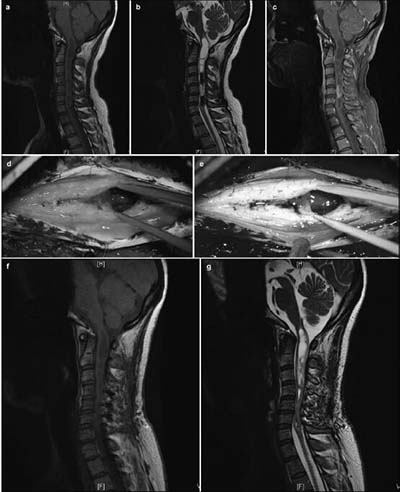

20171023161638 Figure 2 Pre- and postoperative magnetic resonance imaging of intramedullary ependymomas at C2–T2, and intraoperative observations. (a) Preoperative sagittal T1 image reveals spinal cord thickening. (b) T2 image shows high intramedullary signal intensity at C2–T2, but no signal at either end. (c) Enhanced scanning reveals distinctive enhancement of the tumor mass and cyst wall. Tumor ends, as micrographed using white light (d) and fluorescence (e). (f) Cysts at the tumor ends, microscopically probed with white light, do not show the tumor. (g) Distinct cyst walls are evident under fluorescent illumination, revealing a suspicious tumor that was removed. At 3 months, the sagittal T1 (h) and T2 (i) images and the enhanced scan (j) reveal no evidence of tumor residuals or relapses.